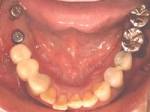

両側5歯症例

両側5歯症例両側5歯症例両側5歯症例 主訴-義歯のバネが壊れて手前の歯が痛んできた。 術前(旧義歯装着、鏡像) 術前(下顎粘膜面、鏡像)術前(下顎粘膜面、鏡像)術前(下顎粘膜面、鏡像) 術前レントゲン術前レントゲン術前レントゲン 術前口腔内(正面観)術前口腔内(正面観)術前口腔内(正面観)

術後(鏡像)術後(鏡像)術後(鏡像) 術後口腔内(正面観)術後口腔内(正面観)術後口腔内(正面観)もう入れ歯は要らなくなりました。 術後レントゲン術後レントゲン術後レントゲン